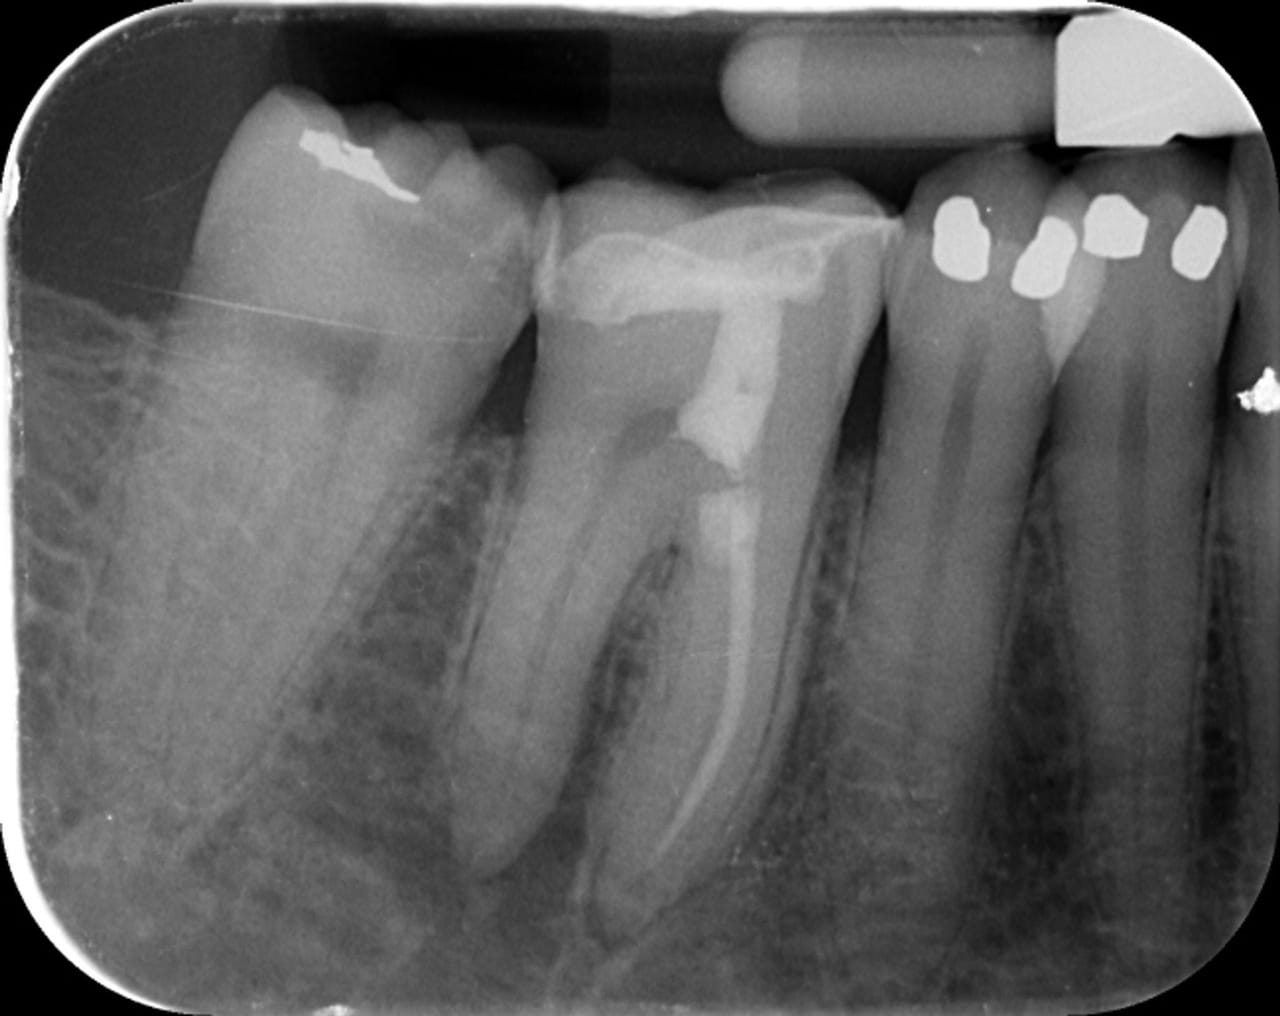

Cette lésion est clairement visible sur la radiographie préopératoire (Fig.1). Néanmoins, l’analyse de ce cliché réalisé avec un angulateur selon la technique des plans parallèles, ne permet pas de délimiter clairement les bords de cette lésion, ni d’en définir la profondeur et ses rapports avec l’endodonte de la dent concernée.

Fig.1 : Radiographie préopératoire – cliché pris selon la technique des plans parallèles avec un angulateur.